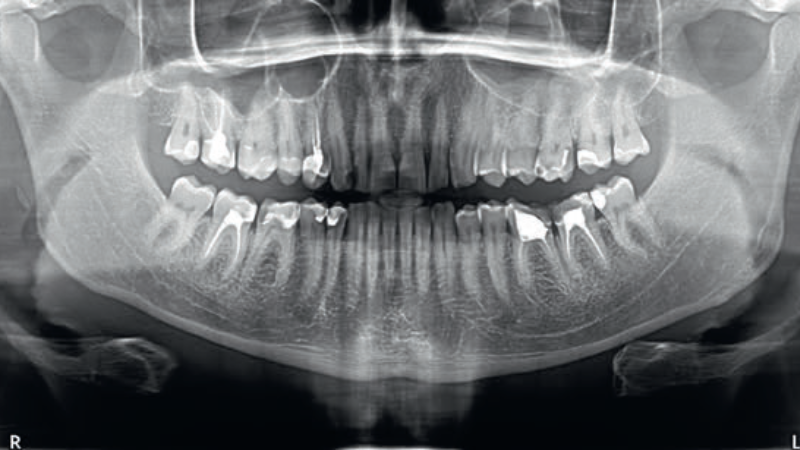

Streszczenie: Współczesna stomatologia daje możliwości zachowania przez całe życie naturalnych zębów pacjenta. Jedną z częstszych sytuacji klinicznych w gabinecie stomatologicznym są wskazania do ponownego leczenia kanałowego. Zęby po leczeniu endodontycznym niejednokrotnie wymagają zaopatrzenia protetycznego, ponieważ są one osłabione, odwodnione i bardziej podatne na złamania. Zastosowanie uzupełnień protetycznych wymaga wzięcia pod uwagę kwestii estetycznych i biomechanicznych. Obecnie dzięki zastosowaniu technik stomatologii adhezyjnej i cyfrowej można wpłynąć pozytywnie na rekonstrukcję zęba. Stosowanie skanerów wewnątrzustnych zapewnia pacjentom większy komfort podczas zabiegów, skraca czas pracy oraz upraszcza procedury kliniczne. Skanowanie i projektowanie cyfrowe zapewnia również precyzyjne dopasowanie uzupełnienia do przygotowanej powierzchni zęba, co przekłada się na wyższy komfort pacjenta oraz trwałość odbudowy.

Summary: Modern dentistry offers opportunities to preserve natural teeth for life. One of the more common clinical situations encountered by dentists are indications for retreatment of root canals. Following endodontic treatment, teeth frequently necessitate prosthodontic restoration due to the deterioration of their structure, resulting in increased vulnerability to fracture. The utilisation of prosthodontic restorations requires a [...]